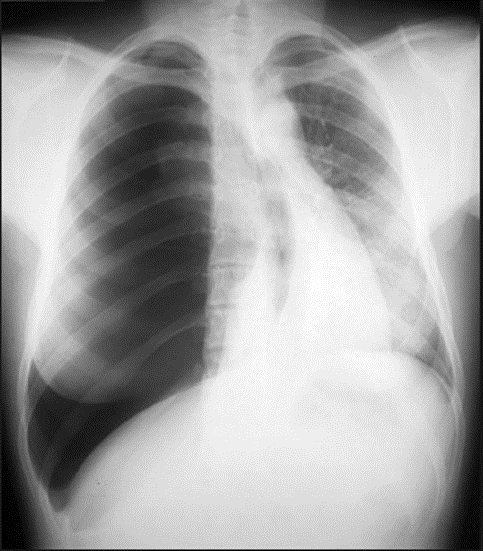

What is this x-ray showing?

What 3 findings suggest this?

Right Tension Pneumothorax w/

Right Pleural Effusion

Flattening of left diaphragm

Deviated to the right

Left pneumothorax

Normal CXR